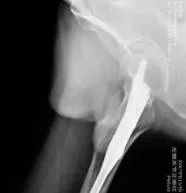

患者,48岁,有脑梗死后遗症且左侧肢体偏瘫,在家走路时不慎摔倒致左髋关节疼痛、活动受限入院。入院后查左侧髋关节X线片示:左股骨粗隆间骨折。骨外一科医疗团队在孙波主任主持下行病例讨论,并制定手术方案,决定行左股骨粗隆间骨折闭合复位内固定术(PFBN)。

通过医护加强多模式镇痛及快速康复技术,术后第2天,患者即可下地站立,在医护人员的帮助下,患者下地部分负重行走;术后13天顺利出院,患者及家属对医护人员表示由衷的感谢。术后复查X线片:骨折对位及内固定位置良好。